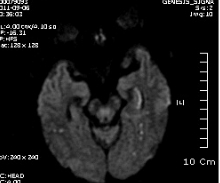

B MRI 촬영 결과는 좌측의 corona radiata, Lt temporo-occipital lobe 의 subcortical area 의 optic radiation 부위를 비롯한 여러 군데 점상 병변. N/S 정주하고 Aspirin 투여 시작, 혈압약은 지속 투여, SBP 160정도로 유지.

좌측사진은 PCA 영역. 우측사진은  AchA 영역의 post. periventricular corona radiata (Stroke 4ed p199, Fig 9-3 과 동일)

진행하였다면 우선 DWI follow up  중요합니다. 아마도 corona radiata 영역이 진행한 것 같지만요..

DWI coronal or saggital view 보면 분명하겠지만 이 사진으로 보니 PCA territory infarction으로 모두 설명되는 것 같습니다. PCA 영역에 hypoperfusion으로 병변이 크지는 것 같습니다. 5-7일 지나야 안정기에 들어갈 것 같습니다.